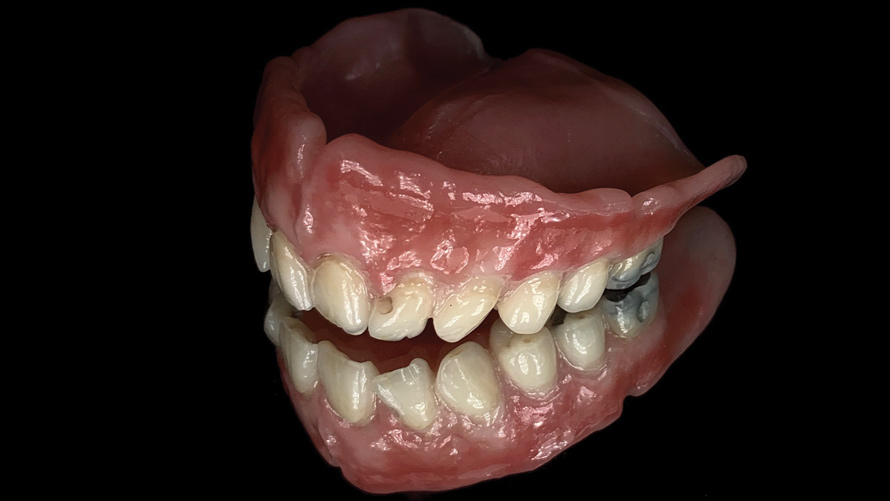

(23.) Smartphone dental light attachments are useful for product photography.

Figure 23

(24.) Smartphone dental light attachments are useful for product photography.

Figure 24

(25.) Smartphone dental light attachments are useful for product photography.

Figure 25